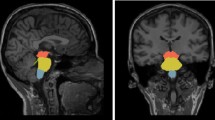

The hippocampus was segmented into cytologically-defined subfields (Fig. 1A) using the FreeSurfer image analysis suite [43]. The pre-processing pipeline included the removal of non-brain tissue, segmentation of the subcortical white matter and deep grey matter structures, intensity normalization, tessellation of the grey matter–white matter boundary, and automated topology correction. The hippocampal stream of the FreeSurfer package was used for the delineation of the following hippocampal subfields: CA1, CA2/3, CA4, fimbria, hippocampal fissure, presubiculum, subiculum, hippocampal tail, parasubiculum, molecular layer; granule cell layer of the dentate gyrus (GC-DG), and hippocampal–amygdala transition area (HATA) [46].

While differences in overall subcortical volume differences did not reach significance (Table 2), mediodorsal-paratenial-reuniens in the left thalamus and pulvinar-limitans atrophy in the right thalamus was detected in asymptomatic C9orf72 hexanucleotide repeat expansion carriers compared to gene-negative family members (Table 3.). Furthermore, higher sensory nuclei volumes were identified in C9orf72 hexanucleotide repeat expansion carriers compared to both gene-negative controls and SOD1 mutation carriers in both thalami. Effect sizes are illustrated in Fig. 1. Differences in amygdalar nuclei and hippocampal subfield volumes did not reach significance. Relevant output statistics, univariate p value, and effect sizes are summarised in supplementary tables 1–2.